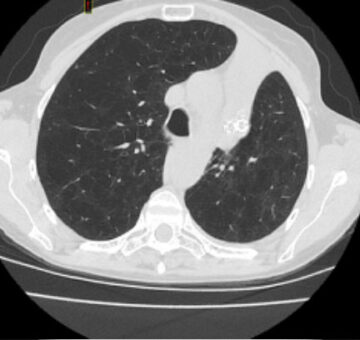

Successful atelectasis of the right middle lobe with 80% fissure completeness score